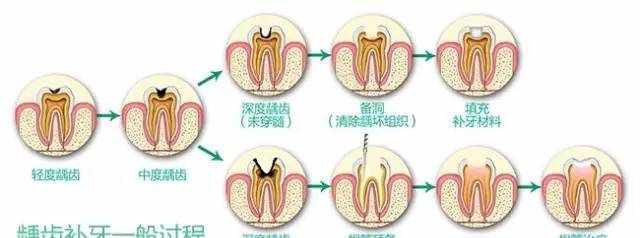

龋齿的治疗

牙齿的早期龋齿(白斑时期),可以通过日常使用含氟牙膏、护牙素,定期看牙医进行涂氟来进行修复。

在龋坏未累及牙神经时,单纯的补牙就足以解决问题。

如果疾病发展到牙髓炎甚至根尖周炎,则需要进行根管治疗后做全冠保护牙齿,从而达到保存功能性牙齿的目的。

根管治疗需要复诊2-3次,间隔一周。患者为此所付出的时间、精力、财力相比较单纯补牙增加许多。

根管治疗

根管治疗的过程:(见图)

根管预备--去除牙齿腐坏组织,打开牙髓腔,用一套金属锉将根管扩大并用消毒药水将其中的感染碎屑冲洗出来。

根管充填--使用根管充填材料将清理干净后的根管系统封闭起来。

根管消毒封药--如果根管里有感染残留,医生可能会在根管内封抗菌药,下次就诊时根据感染是否得到控制,决定是否做根管充填。

根管治疗的过程:(见图)

根管预备--去除牙齿腐坏组织,打开牙髓腔,用一套金属锉将根管扩大并用消毒药水将其中的感染碎屑冲洗出来。

根管充填--使用根管充填材料将清理干净后的根管系统封闭起来。

根管消毒封药--如果根管里有感染残留,医生可能会在根管内封抗菌药,下次就诊时根据感染是否得到控制,决定是否做根管充填。